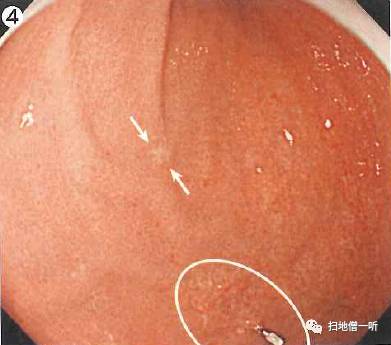

A:多发性病变见于图4。HP未感染类癌。

外院发现的病变位于白色圈内,在其口侧可见小片发白粘膜(箭头处),非萎缩粘膜内褪色性病变,怀疑未分化癌。